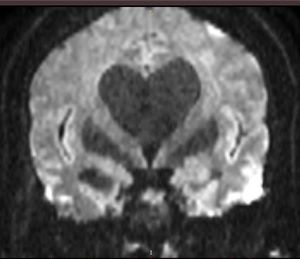

MRI and DWI love. MRI of hydrocephalus based on 2mm isotropic DWI reformatted in coronal plane. Shared by Anastasios Karatopis.